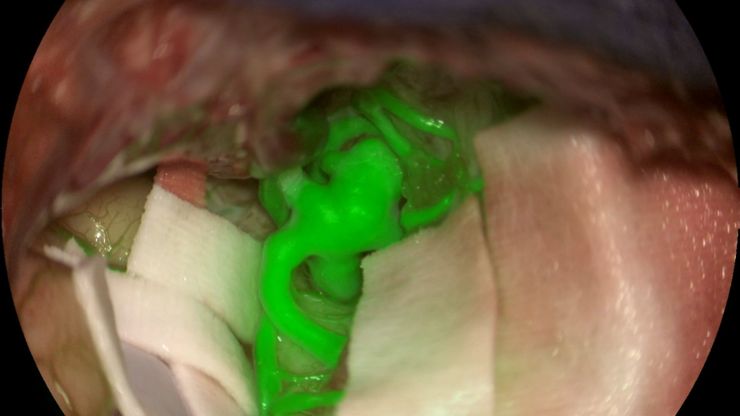

Aneurysm shown with GLOW800 AR fluorescence application. Image courtesy of Prof. Jacques Guyotat, Hôpital Neurologique Pierre Wertheimer, Lyon

How AR Fluorescence Imaging Supports Neurovascular Surgery

In this article, we explain how fluorescence imaging works in vascular neurosurgery and explain the benefits of the GLOW800 Augmented Reality fluorescence application.